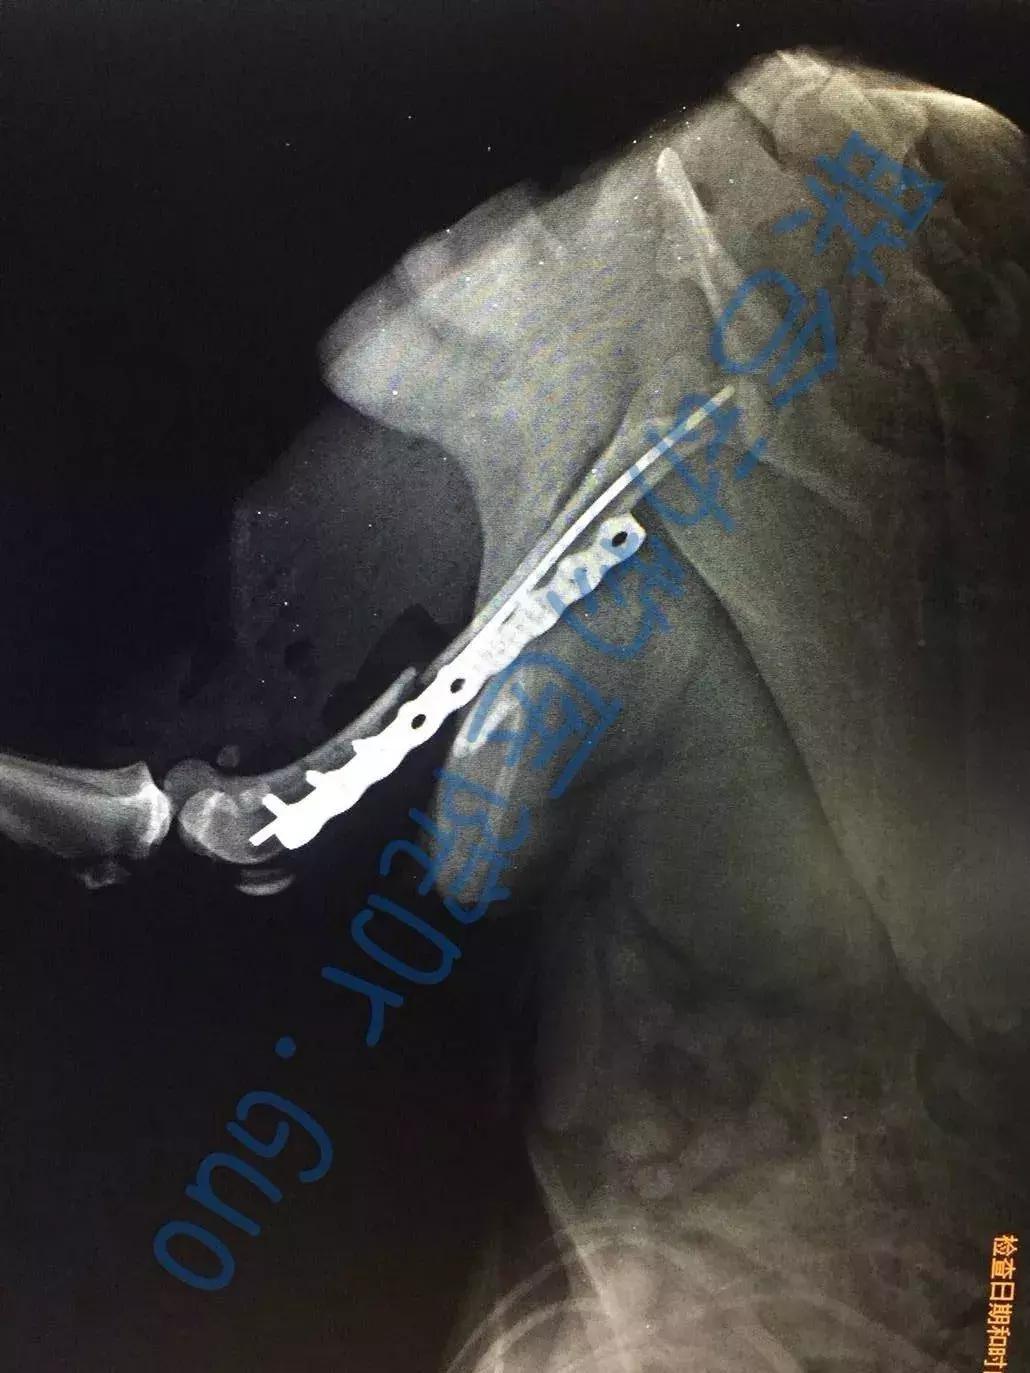

术后X线片

六一小朋友的年龄仅有3个月,体重仅1kg,对于这样的幼猫,陈旧性骨折发生二次骨折的内固定手术无疑是一个严峻的挑战。六一的主治医生张海峰院长使用接骨板板对六一进行了骨折的内固定。

接骨板(钢板、钛合金板)几乎可以用于任何部位的骨折。文章开头讲到的六一就是用这种方式进行的固定。接骨板可按不同的部位可以设计成不同的形状,同时,根据力学原理的不同还分成不同的种类。